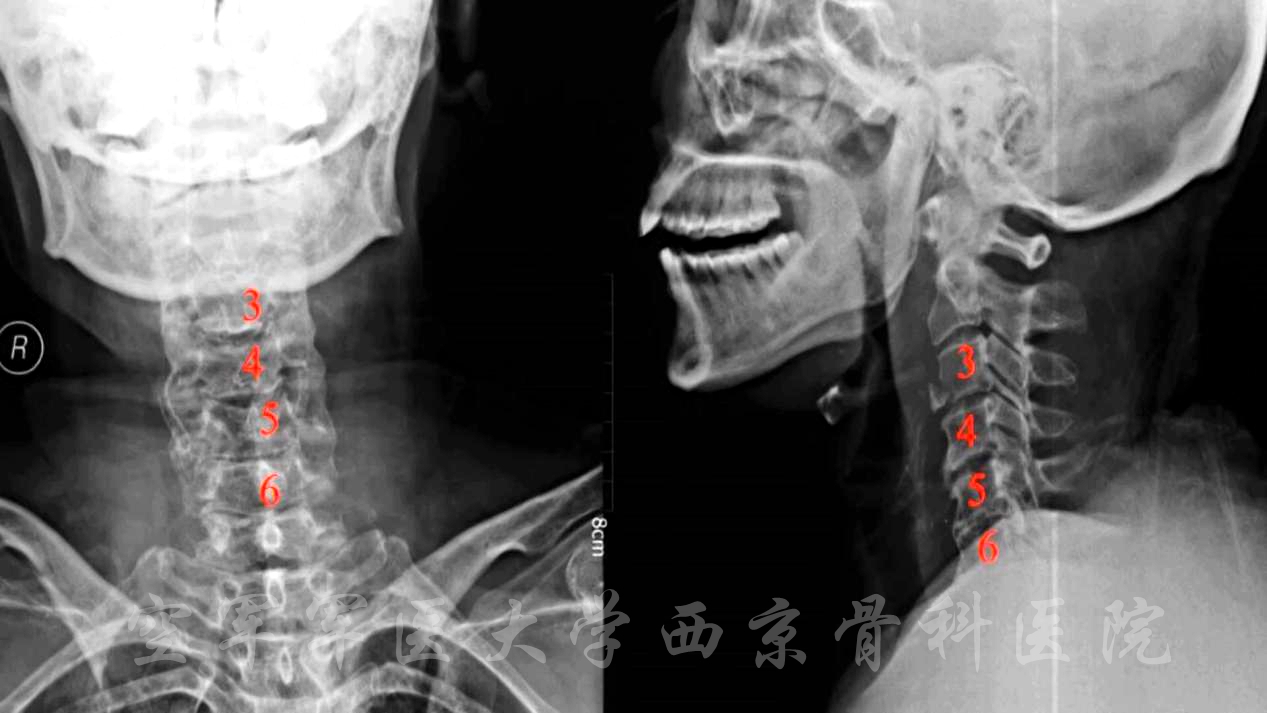

术前X线正侧位片

术前CT